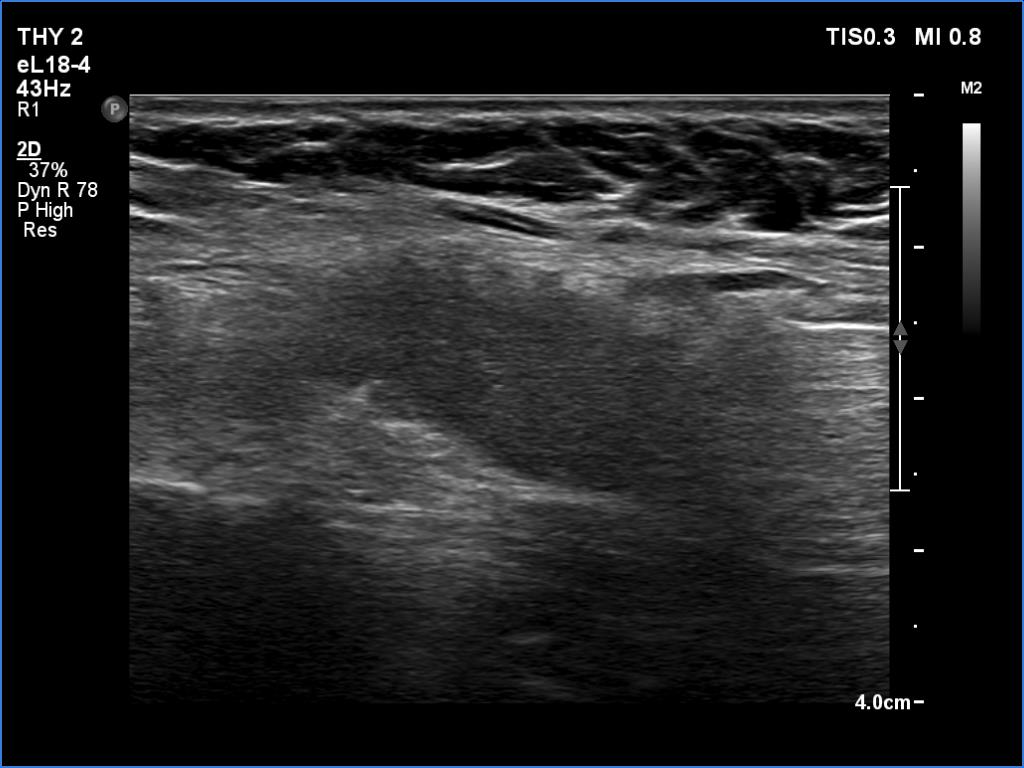

First examination (first and second rows of images):

Clinical data: A 62-year-old woman was operated on Graves' disease 15 years ago. She did not require replacement therapy. She was now referred for an evaluation of palpation and 7 kg weight loss and recurrent nodule described on ultrasonography.

Ultrasonography. A diffusely hypoechogenic thyroid was found with small more hypoechogenic areas. The hypoechogenic area was surrounded with echonormal tissue. This pattern was interpreted falsely as a nodule by a previous examiner. The vascularization was average.

Comment. It is worth analyzing the ultrasound presentation - a large hypoechogenic area is surrounded with a thick echonormal rim. Although this pattern seems to be a nodule, it is one of the most characteristic appearances of a subtotally resected thyroid.